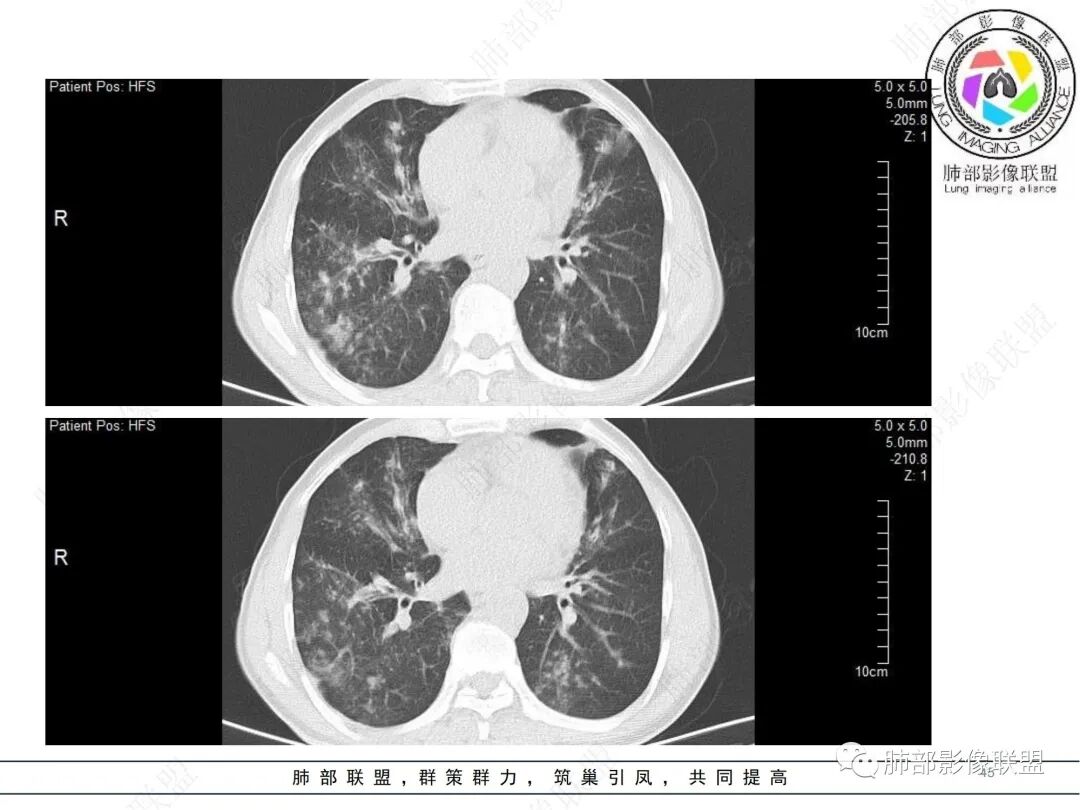

58岁男性,咳嗽胸闷3天,咳较多褐粘液痰,无发热。有2型糖尿病病史。白细胞与中性粒细胞升高。CRP升高。鳞状上皮细胞癌抗原轻度升高。结核T细胞免疫斑点实性阳性。肺炎支原体、衣原体IgG轻度升高。支气管镜显示支气管炎性改变、右肺下叶背段管腔狭窄。2.影像特点:

2022.6.24CT显示两肺弥漫性段、亚段支气管壁增厚(两肺各叶都累及),增厚的支气管壁外可见沿着支气管分布的渗出、实变影。另外远端肺内亦可见多发树芽影、结节影,其边界欠清晰。右肺下叶基底段局部胸膜下亦可见小斑片影,边界不清。2022.6.27CT显示两肺增厚的支气管壁外的渗出实变影明显增多、范围更广。远端肺内病灶亦增多、范围增大。部分位于胸膜下的病灶可见侧向融合趋势。3.病例分析: